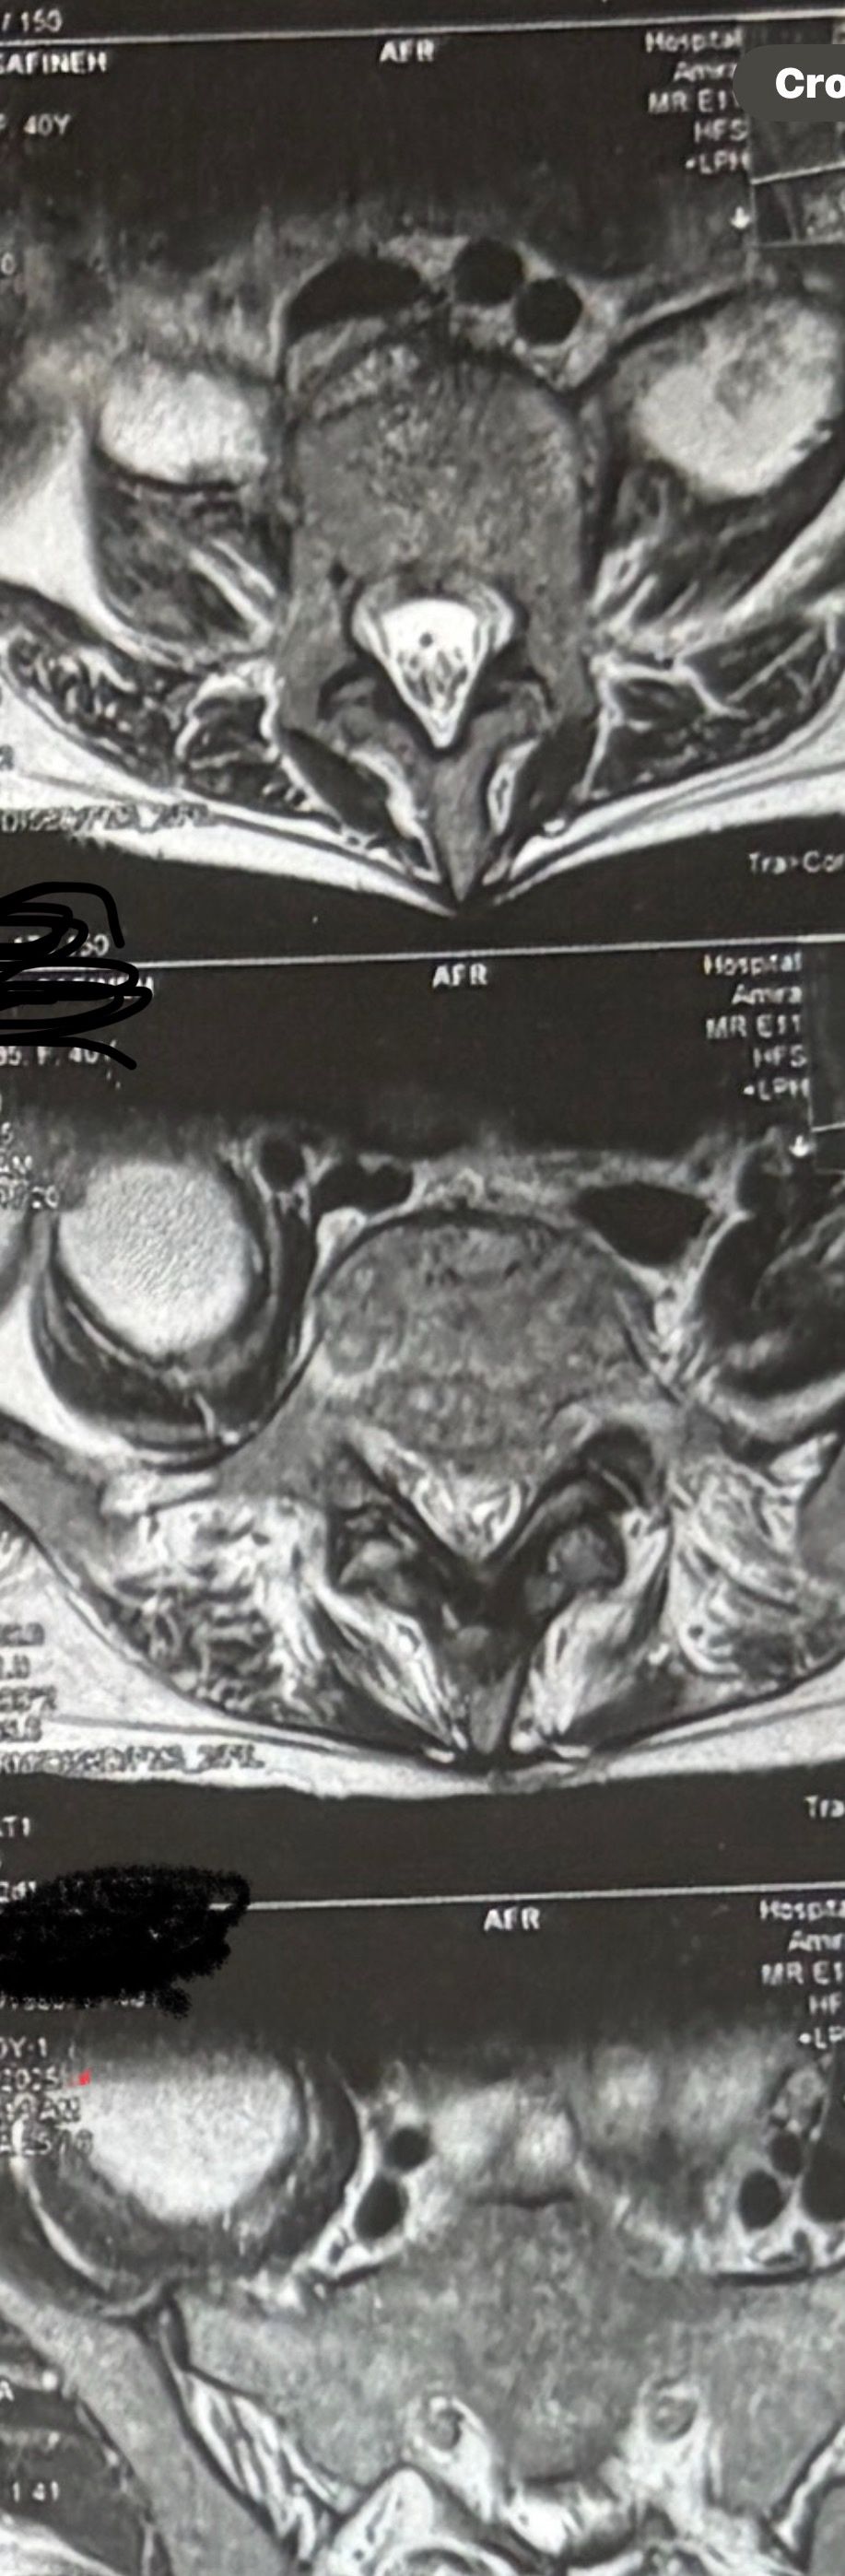

46 years old female patient presented to my clinic yesterday june 1/2025 with LBP and radicular L leg pain for several months which hasn’t responded to physio 2 neurosurgeons have visited her and didn’t suggest any surgery Neurological exam was unremarkable please see her mri/ emg/ncv and her huge tarlov cyst and possible L IVF L4-5 hyperbulge I ordered sacrum mri and ct scan and new emg/ncv and asked her with her sacral Ct scan and MRI first sees another two famous neurosurgeons and see if that large cyst is the reason for her pain if not i can work on her L4-S1 area Do you think her radicular pain can originate from her large cyst in sacrum? Do you consider surgery and removing her sacral cyst?